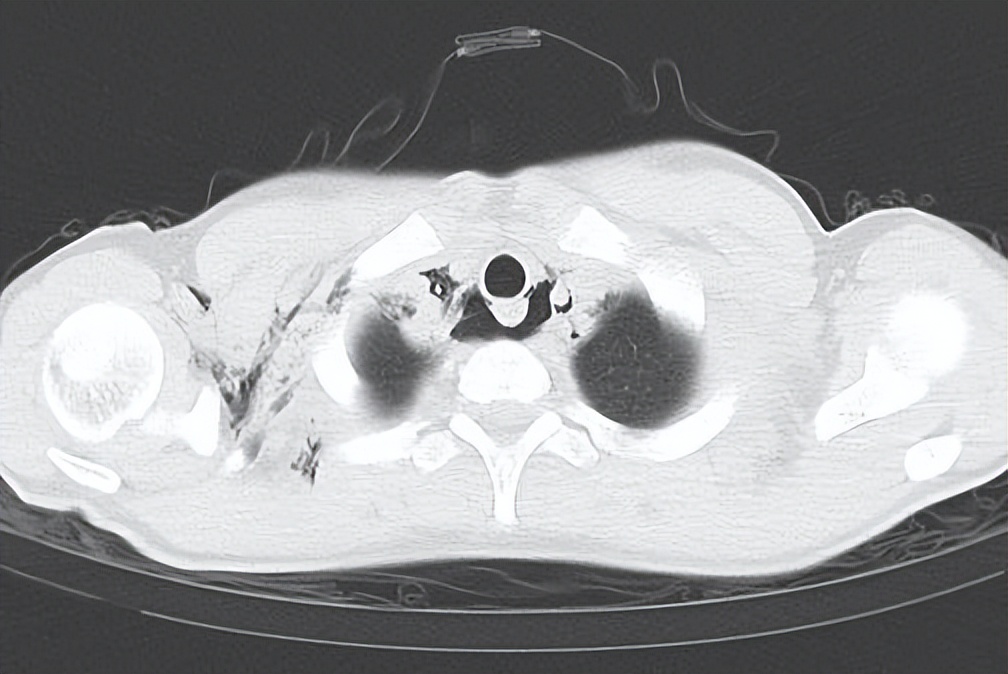

“小福,去查个胸部CT吧,有可能纵隔气肿了。”急诊医生没把话说得太满。

胸部CT检查:纵隔及颈部气肿,右侧胸壁软组织积气。